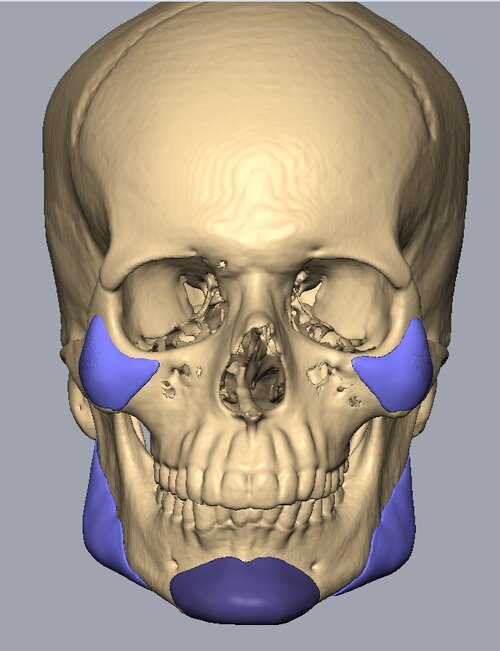

Recieved the draft 1 of the design, what changes should i ask for?? a couple of things i can think of are malar implants not giving enough lateral protrusion, gonion flaring.

I also am planning to include infra implants as well.